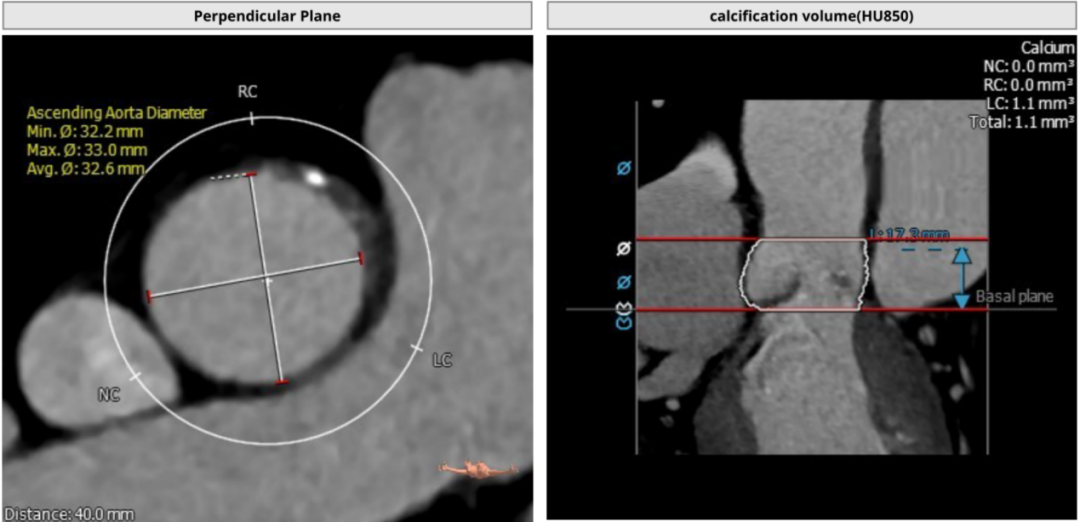

术前CT测量

瓣环:24.4mm;LVOT:22.7mm;

瓦氏窦:32.0*31.4*32.0mm;

升主动脉:32.6mm;左冠高度:17.3mm;

右冠高度:17.3mm;钙化积分:1.1mm³;

瓣环与水平面夹角:34°;